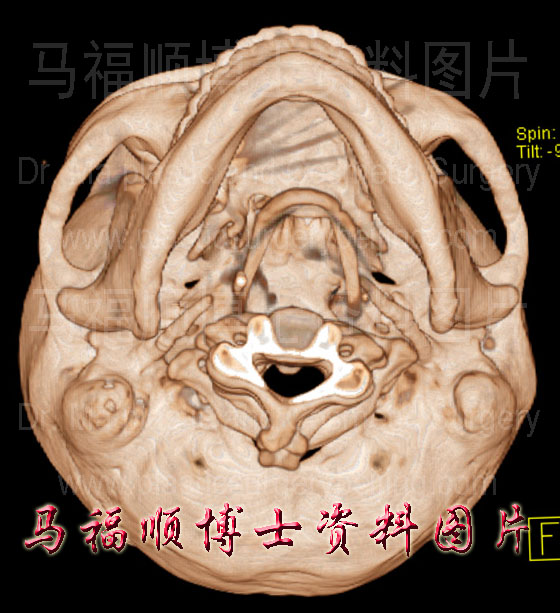

颧弓宽者的三维CT重建图片上显示,颧弓向两侧面突出。右侧图片为颧弓窄的的三维CT片中示颧弓不向两侧突出。